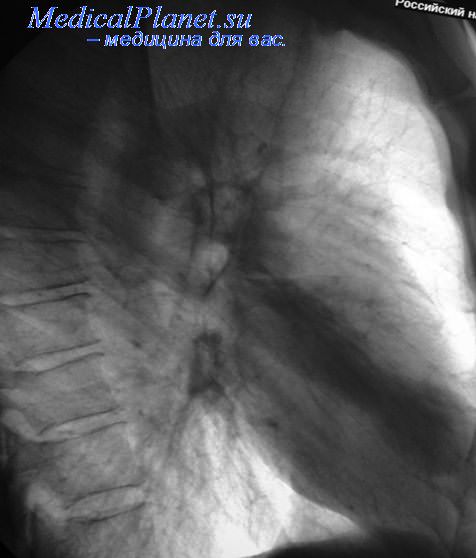

Рентгенологически при легочной и легочно-медиастинальной формах саркоидоза Бека обнаруживают в средних отделах лёгких, пригилюсных зонах, густую мелкоочаговую диссеминацию. Область верхушек легких, а также диафрагмальных участков легочных полей обычно свободна от изменений. В отдельных случаях видна значительная густота очаговых изменений на всём протяжении легочных полей. Симптом локальной тени.. Гилюсы при этом увеличены и ясно выступает полицикличе- ский характер их контуров. При легочной форме корни лёгких могут быть нормальных размеров. При диссеминированном туберкулёзе гилюсы не увеличены. Отметим, что у больных саркоидозом тени увеличенных опухолевидных узлов, не столь выражены, как при медиастинальной форме болезни. Увеличенные гилюсы чаще всего бывают с двух сторон. У больных диссеминированным туберкулёзом очаговые тени расположены обыч- но в верхних и средних отделах, количество их убывает книзу (апико-каудальное распро- странение). При подострой форме выражена перифокальная реакция вокруг очагов, не- редко наличие распада в виде «штампованных» или «очковых» каверн.

Дифференциальные рентгенологические признаки туберкулеза с саркоидозом базируются на 3 пунктах: на состоянии корней легких; на локализации и характере очаговых изменений; на особенностях легочного рисунка.

Двустороннее расширение корней легких наблюдается при саркоидозе II—III стадии в 70-80 % случаев, одностороннее — в 20-30 % случаев, при туберкулезе — в 2,4 % случаев. При саркоидозе очаги в легких расположены симметрично и локализуются чаще всего в передних и наружных сегментах легких. При диссеминированном туберкулезе высыпания неравномерные и наблюдаются преимущественно в задних сегментах. Легочный рисунок при саркоидозе симметрично усилен, избыточен, при туберкулезе -неравномерен. При саркоидозе распад бывает редко, лишь в III стадии, а при туберкулезе он определяется в среднем у половины больных.